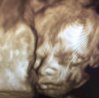

så finLillesøster i uke 25![]()